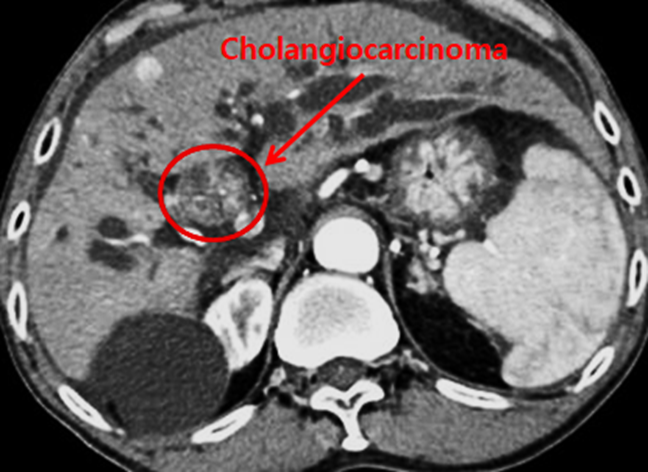

I. Definition and Overview

Cholangiocarcinoma (CCA) is a malignant epithelial neoplasm that arises from the biliary ductal epithelium. It represents a diverse group of cancers characterized by distinct genetic, anatomical, and clinical profiles, and is broadly classified into intrahepatic (iCCA), perihilar (pCCA), and distal (dCCA) subtypes, based on the anatomical location within the biliary tree.

2. Computed Tomography (CT)

• iCCA: Hypodense mass with peripheral rim enhancement on arterial phase, progressive centripetal enhancement on delayed phases.

• pCCA/dCCA: Poorly enhancing mass at biliary bifurcation or distal duct, causing upstream biliary dilation.